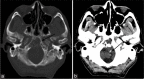

Figure 4:

Plain CT brain. An lobulated mass centered at the right petroclival region (dark arrow) with extension into the right posterior ethmoid sinus and right sphenoid sinus (white arrow).